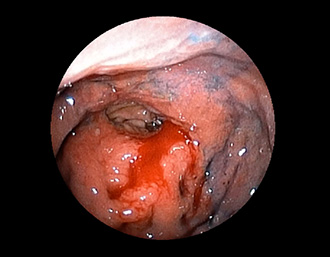

症例2:胃がん(66才男性)

術後胃(B-Ⅱope magen:十二指腸潰瘍手術)。吻合部の後壁側、軽度陥凹の白色病変を認める。生検:Group 5、Signent-ring cell carcinoma(印環細胞癌)と診断[早期胃癌]。高次医療機関へ紹介となり、残胃全摘術(リンパ節郭清)を行いました。

(通常画像)